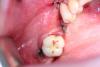

ВИТА Опубликовано 22 августа, 2012 Автор Поделиться Опубликовано 22 августа, 2012 мне кажется в последнем случае будет по лучше результат......и методика расщепления та же, что и в самом первом случае....и всё таки , как сказал, Олег "расщепление там все же происходит, лепестки несколько расходятся." Ссылка на комментарий

DShu Опубликовано 23 августа, 2012 Поделиться Опубликовано 23 августа, 2012 с другой стороны - такВ области мезиального импланта расщепление вижу, у дистального нет. Если бы там было расщепление, имплант бы полностью был окружен своей костью, а у вас вестибулярка все равно оголена получилась.И я все таки сторонник фиксировать мембрану, чтобы обеспечить полную иммобилизацию материала. В вашем случае есть риск его сползания.Я бы сделал тут однозначно блок, или импланты+биоос+цитопласт (или титановая мембрана) Ссылка на комментарий

Sahan Опубликовано 24 августа, 2012 Поделиться Опубликовано 24 августа, 2012 Вита,работа красивая..:-) Был на курсе у Анны Парицки,она такие вещи закрывает кашицей из байо-осса и коллагеновой мембраной сверху,при чем,её на винты не фиксирует.Ушивается все сперва п-образными швами,потом узловыми.С каркасной мембраной все таки надежней, тем более достаточно большой объем нужно закрыть. Тем более основное давление на графт лоскут оказывает в коронарной части имлантата и без каркаса в том месте остается меньше всего графта. Ссылка на комментарий

andr86 Опубликовано 24 августа, 2012 Поделиться Опубликовано 24 августа, 2012 ну можно и так.... Доброго времени суток. Разрешите вопрос. Как так точно удается подогнать заглушку под мембрану!? Или Вы просто делаете небольшое отверстие в мембране под заглушку и так крутите к винту? Заранее спасибо за ответ. Ссылка на комментарий

ВИТА Опубликовано 24 августа, 2012 Автор Поделиться Опубликовано 24 августа, 2012 (изменено) Доброго времени суток. Разрешите вопрос. Как так точно удается подогнать заглушку под мембрану!? Или Вы просто делаете небольшое отверстие в мембране под заглушку и так крутите к винту? Заранее спасибо за ответ.делаю отверстие в мембране под заглушкуну вот ещё Изменено 24 августа, 2012 пользователем ВИТА 1 Ссылка на комментарий